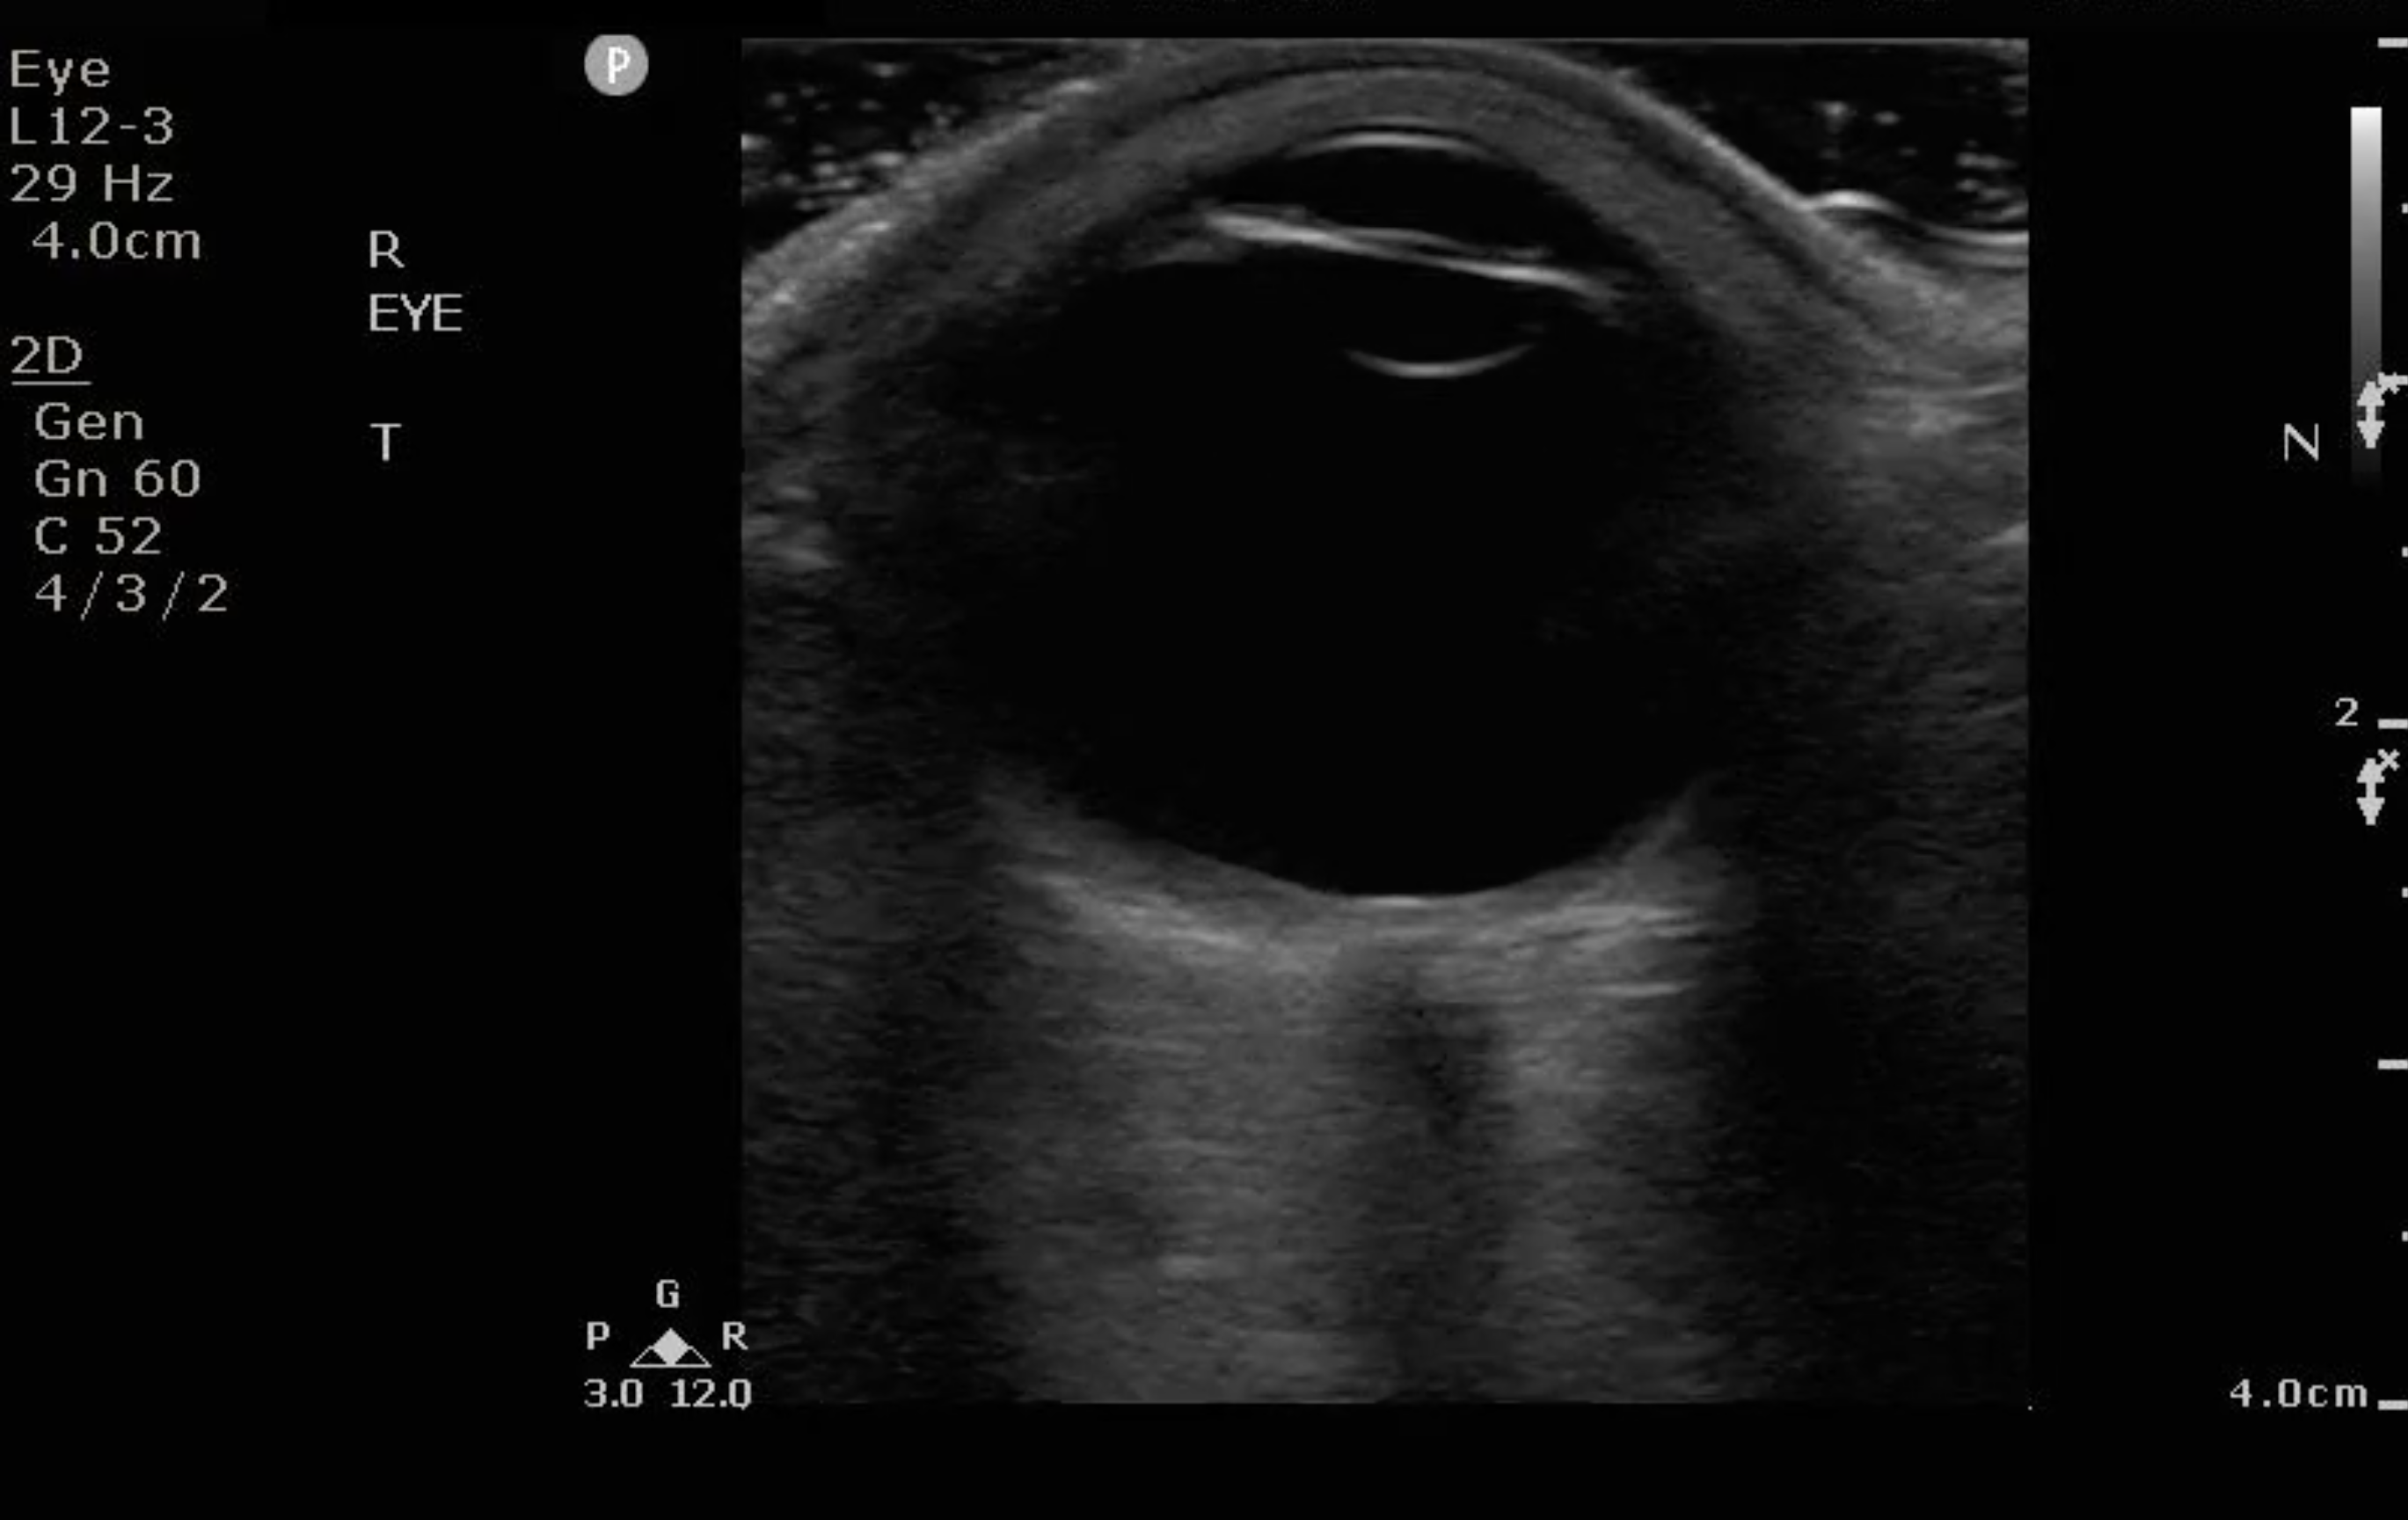

- Figure 3. Ultrasound image of a normal eye.

Normal Findings

- Because the ocular chamber is fluid-filled, under ultrasound, it will appear as a round, anechoic structure.

- The most anterior structure seen, after the layer of ultrasound gel, is the eyelid.

- Just deep to the eyelid is the cornea and the anterior chamber. If too much pressure is applied during the ocular ultrasound examination, the anterior chamber may become compressed. It is important to avoid applying direct pressure to the eyelid.

- If the patient attempts to look down during the exam, you may be able to visualize the iris and pupil.

- The lens appears as a hyperechoic, curved line, located deep to the iris. If the patient has undergone cataract surgery, you may see two thin, hyperechoic parallel lines instead of the concave hyperechoic line.

- Normal vitreous humor will appear anechoic.

- The vitreous, retina, and choroid are located along the inside of the globe. Normally, you cannot differentiate one from the other.

- The most far field identifiable structure is the optic nerve. The parallel hyperechoic lines are the optic nerve sheath, since the optic nerve is hypoechoic and nondistinctive.